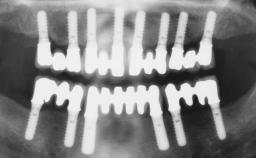

Immediate Loading of Six Implants in the Maxilla and Final Restoration with a Full-Arch CAD/CAM Zirconia FDP

# of Implants 6

Type of Implants One-Piece

Modality 6+ implants with immediate loading